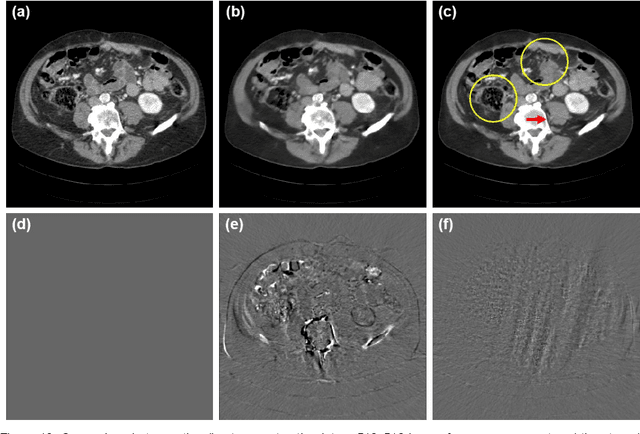

Abstract:By the ALARA (As Low As Reasonably Achievable) principle, ultra-low-dose CT reconstruction is a holy grail to minimize cancer risks and genetic damages, especially for children. With the development of medical CT technologies, the iterative algorithms are widely used to reconstruct decent CT images from a low-dose scan. Recently, artificial intelligence (AI) techniques have shown a great promise in further reducing CT radiation dose to the next level. In this paper, we demonstrate that AI-powered CT reconstruction offers diagnostic image quality at an ultra-low-dose level comparable to that of radiography. Specifically, here we develop a Split Unrolled Grid-like Alternative Reconstruction (SUGAR) network, in which deep learning, physical modeling and image prior are integrated. The reconstruction results from clinical datasets show that excellent images can be reconstructed using SUGAR from 36 projections. This approach has a potential to change future healthcare.